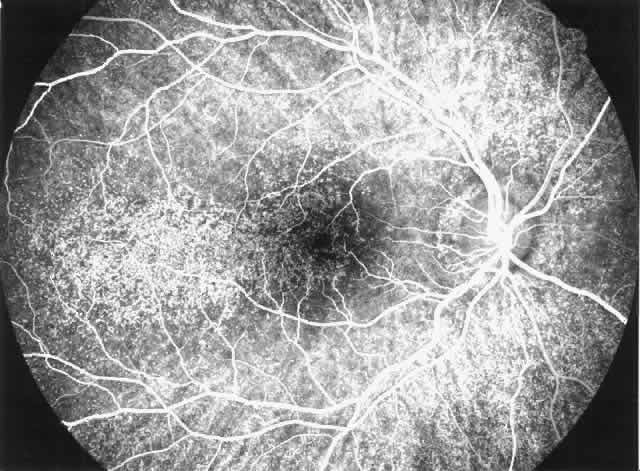

Drusen-like lesions and retinal pigment epithelium damage have also been recognized as a feature of MPGN type II.72–79 In a fluorescein angiographic study of 26 patients who had biopsy-proven MPGN type II, specific fundus lesions were identified in 24 patients (92%).79 Two adolescents with a history of renal disease of 13 months and 2 months had normal fundi. Small-sized lesions similar to small hard drusen were observed in all 24 patients with a history of renal disease lasting for 16 months or more (Fig. 6). In all 15 subjects with a history of renal disease of at least 12 years, larger drusen-like lesions were also noticed. In all 11 patients with renal disease persisting for 18 years or more, drusen occupied most of the fundus and areas of geographic atrophy were seen as well. Foci of new vessels and disciform scarring were observed in eight eyes of five patients with a renal history of 15 years or more (Fig. 7). Most eyes that did not show subretinal neovascularization had normal or nearly normal vision and visual fields. Three patients, however, exhibited ocular symptoms, which were related to pronounced macular atrophic changes, hypertensive retinopathy, and cataracts. The type of fundus lesions was statistically correlated (p<0.0001) with the duration of the renal disease, but not with age, sex, or renal insufficiency. Fundus changes between first and last visit as well as cross-sectional studies suggest a slow progression of retinal disease, which is probably independent of treatment and age of the patient.77–79

Fig. 6. Specific fundus lesions of membranoproliferative glomerulonephritis type II in a 12-year-old child with renal disease since the age of 3 years. The fluorescein angiogram shows numerous small lesions similar to hard drusen. (Leys A, Vanrenterghem Y, Van Damme B et al: Fundus changes in membranoproliferative glomerulonephritis type II: A fluorescein angiographic study of 23 patients. Graefes Arch Clin Exp Ophthalmol 229:406, 1991)

Fig. 7. Fluorescein angiographic changes in a 32-year-old patient with renal signs of membranoproliferative glomerulonephritis type II since the age of 9 years. Numerous small and larger drusen-like lesions, atrophic changes, and a small infrafoveolar subretinal neovascular membrane that was successfully treated with argon laser coagulation can be seen. (Leys A, Michielsen B, Leys M et al: Subretinal neovascular membranes associated with chronic membranoproliferative glomerulonephritis type II. Graefes Arch Clin Exp Ophthalmol 228:499, 1990)